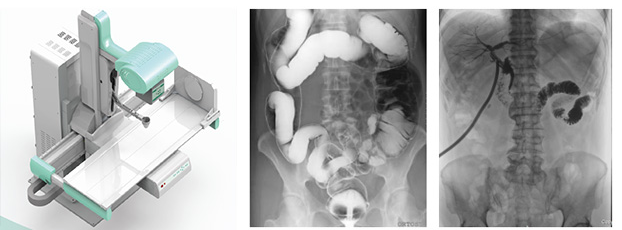

多功能dr集合拍片、造影、胃腸、透視等多種功能。可以理解為一種不同角度觀察器官運動的X光視頻,可以從不同的角度、時間來觀察器官的運動,診斷準確率會大大提升。面對常規dr誤診漏診頻繁出現的情況,多功能dr是如何用其產品優勢彌補缺陷的?接下來小編帶大家先來看一組動態臨床案例。

如下圖所示:該患者因吞咽時感到很難受,進食時也經常咳嗽故就醫診斷。使用多功能dr為病人進行消化道造影診斷,要求他吞鋇后發現,食道各段通過順利,形態規則,雙側梨狀窩不對稱左側稍淺,多次吞咽動作后,仍見鋇劑滯留,并見鋇劑進入氣管,屬于會厭征陽性。會厭功能紊亂,鋇劑進入了氣管。

圖為正位:通過動態影像可以清楚看到鋇劑進入了支氣管道且雙側梨狀窩不對稱

圖為斜位:通過動態影像可以清楚看到鋇劑進入了支氣管道

通過多功能dr可以診斷該病人的癥狀為會厭功能紊亂,鋇劑進入到了氣管。而在動態透視下可以清晰的觀察到鋇劑從何處進入氣管,可清晰顯示食管粘膜結構。使用多功能dr其獨特的視頻采集技術,可實時保存視頻并能實現900萬像素實時點片,才能獲取這樣清晰的病灶點。而常規dr只能拍攝靜態片,且成像效果大打折扣,因此較難確診病灶。